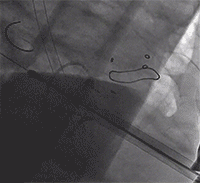

术后造影,结合实时超声评估未见明显二尖瓣反流: